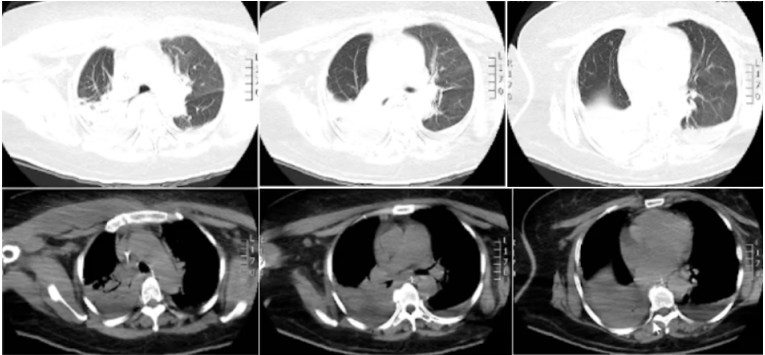

入院时查动脉血气(鼻导管吸氧2 L/min):pH 7.30,PaCO2 49 mmHg,PaO2 83 mmHg,HCO3- 24.1 mmol/L,SaO2 95%。血常规:WBC 13.13×109/L,Hb 123 g/L,NEU% 91.2%(↑)。PCT>100.0 ng/ml,CRP>200 mg/L。CREA 287.0 μmol/L,BUN 24.90 mmol/L。查骨盆X线示右股骨上段骨折内固定术后改变,双侧股骨头缺血坏死并髋关节退变,合并右髋关节脱位。胸部CT(7月28日):双下肺渗出、实变,双侧胸膜下少许胸腔积液(图1)。图1 患者入院后胸部CT